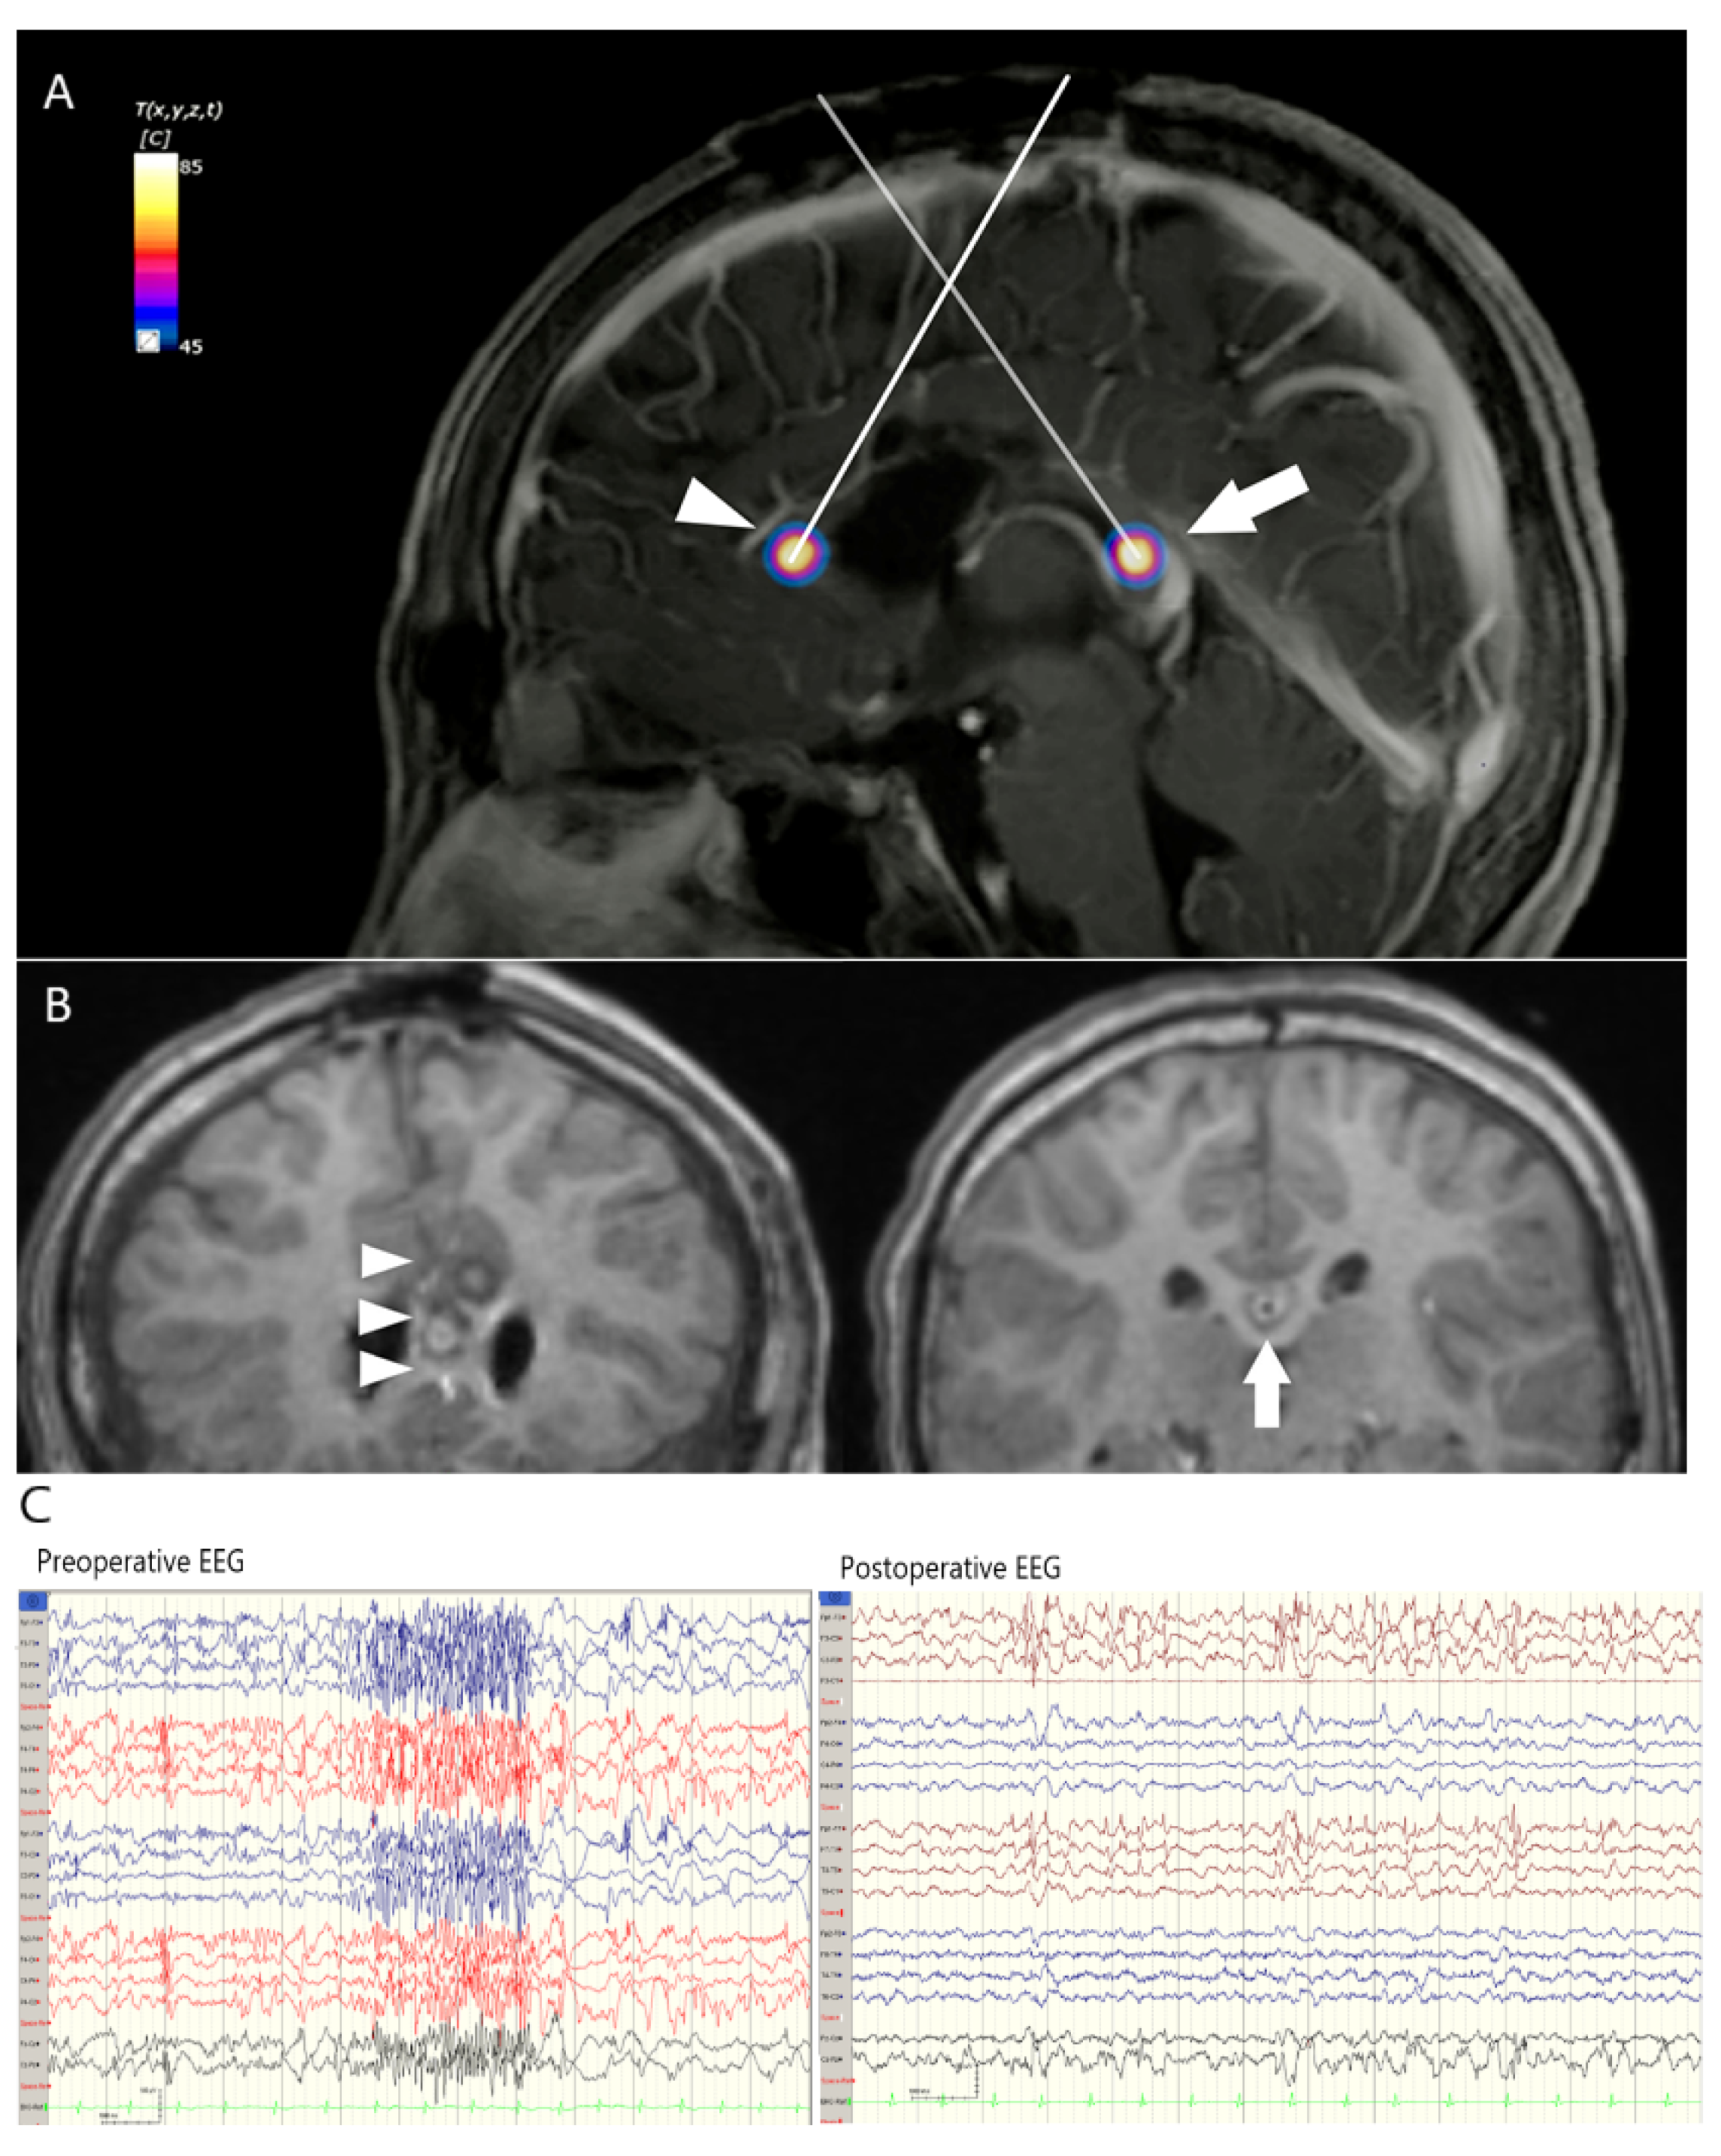

3.3. Case 2. LGS Treated with Anterior CC

| 1 | Male | 28 | Right hippocampal sclerosis | Partial anterior temporal lobectomy | Right remanent hippocampus | 3 | 9949.69 | 9727 (2.3%) | 1 | 2 | none | 1a |

| 2 | Male | 9 | Lennox Gastaut syndrome | Anterior callosotomy | Corpus callosum | 2 | 1867.87 | 1841 (1.4%) | 1 | 4 | none | 4 |